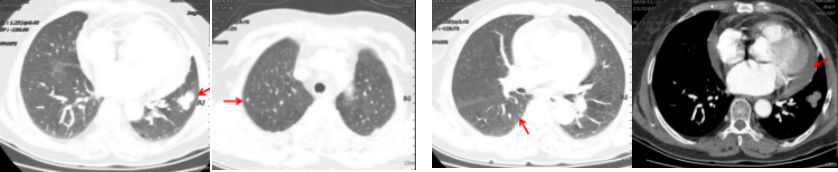

病例简介 该病例是一个肺腺癌(cT4N0M1a)IVa期患者,合并有高血压、冠心病、糖尿病。一线治疗前基因检测结果提示EGFR 19del(+)。一线治疗(埃克替尼片125mg tid)疗效评估为PR、PFS 22个月。一线治疗前基因检测结果提示EGFR 19Del(+)、T790M(+)。后入组D0316(贝福替尼)在EGFR阳性局部晚期或转移性非小细胞肺癌的II期临床试验(IBIO-102项目)。治疗先后由D0316 75mg qd更改方案为D0316 100mg qd,疗效评估为PR,、PFS>32月。至今患者仍持续用药随访中。 Part 1 基本信息 患者:女性;74岁。 主述:反复咳嗽3年,加重伴呼吸费力4月,于2018-1-17就诊。 既往史: 高血压病史10年,服用络活喜、厄贝沙坦氢氯噻嗪、美托洛尔控制血压;冠心病,冠脉支架置入术后4年;糖尿病史2年;否认其他病史。 Part 2 诊疗经过 治疗前辅助检查 2018-1-17查体:血压129/85mmHg;无明显阳性体征。 实验室检查 2018-1-18:血CEA 9.9ng/ml、Cyfra21-1 4.3ng/ml;SCC、NSE、Pro-grp均正常;血常规(Hb 109g/l)、肝肾功能、crp正常。 影像学检查 2018-1-8胸部CT:两肺多发结节,考虑MT伴转移,对照2017-10-4片增大,冠脉钙化,左侧部分肋骨陈旧性骨折,胆囊结石; 2018-1-22腹部B超:脂肪肝倾向,胆囊结石,两肾囊肿,两侧肾上腺未见明显异常回声; 2018-1-21头颅MRI:平扫+增强未见明显异常; 2018-1-23骨ECT:全身骨显像未见明显转移征象。 治疗前病理诊断 肺腺癌(cT4N0M1a) IVa期; 2018-1-18肺穿刺及病理:CK7( ++++ );NapsinA( ++++ ) ;TIF-1(++++);EGFR 19Del(+) ;ALK(-) 。 治疗前临床诊断 肺腺癌(cT4N0M1a) IVa期;PS 1分;EGFR 19Del(+);冠心病、冠脉支架置入术后;高血压病;糖尿病。 一线治疗 治疗方案:2018-1-26开始,埃克替尼片125mg tid。 疗效评估(PR,PFS 22月 ) 埃克替尼治疗11.3个月,两肺结节减少、缩小,达到PR (2018-12-4);治疗22个月,左下肺结节增大、肺内新发小结节、新发心包积液,出现PD(2019-11-21)。 2018-1-18 治疗前基线 2018-12-4 埃克替尼 11.3月(PR) 2019-11-21 埃克替尼 22月(PD) 一线治疗后辅助检查 实验室检查 2019-11-29血CEA 8.4ng/ml ;Cyfra21-1 4.8ng/ml;SCC、NSE、Pro-grp均正常。 2019-12-13血生化肌酐84umol/l;肝功能正常;血常规正常。 影像学检查 2019-12-4头颅MRI平扫+增强:脑内少许腔梗灶; 2019-12-2骨ECT:全身骨显像未见明显转移征象; 2019-12-4腹部增强CT:胆囊结石,右肾上腺及胰腺钙化灶,两肾囊肿。 生理学检查 2019-12-13 ECG:窦性心律,T波改变; 2019-12-13心超:左室轻度增大,左室壁偏厚,左房轻度增大,轻度肺动脉高压伴轻度三尖瓣返流,心包积液,脏层心包增厚,左室舒张功能轻度减退。 一线治疗后病理诊断 2019-11-29分子病理(ARMS法):EGFR 19Del(+) ;T790M(+)。 临床诊断 肺腺癌(cT4N0M1a);IVa期;肺、心包转移;PS 1分;EGFR 19Del(+);T790M(+);冠心病;冠脉支架置入术后;高血压病;糖尿病;肾功能不全。 二线治疗 入组D0316(贝福替尼)在EGFR阳性局部晚期或转移性非小细胞肺癌的II期临床试验(IBIO-102项目)。 治疗方案 2019-12-19开始D0316 75mg qd,于2019-12-24至2020-1-15出现头痛、肩背痛1级AE,自行缓解; 2020-1-13开始D0316 100mg qd; 合并用药有针对糖尿病药物西格列汀片 50mg qd;针对高血压药物氨氯地平5mg qd、厄贝沙坦氢氯噻嗪片1片qd、美托洛尔缓释片47.5mg qd;针对冠心病药物西洛他唑 50mg bid;针对睡眠障碍药物氯硝西泮片1mg qn、艾司酉酞普兰片10mg qd、喹硫平片50mg qd。 安全性评估 疗效评估(PR, PFS>32月 ) D0316 治疗6周就达到PR,患者左下肺靶病灶缩小,两肺小结节稳定、部分缩小(2020-1-28);治疗30周仍为PR,且心包积液减少(2020-7-13);治疗30.5月仍为PR,右下叶背段胸膜下结节缓慢进展(2022-6-30)。 2019-11-21 D0316 治疗前基线 2020-1-28 D0316 治疗6周(PR) 2020-7-13 D0316 治疗30周(PR) 2022-6-30 D0316 治疗30.5月(PR) 2022-6-30腹部增强CT:胆囊结石,右肾上腺及胰腺钙化灶,两肾囊肿。 目前D0316(贝福替尼) 100mg qd 治疗中, PS 1分。